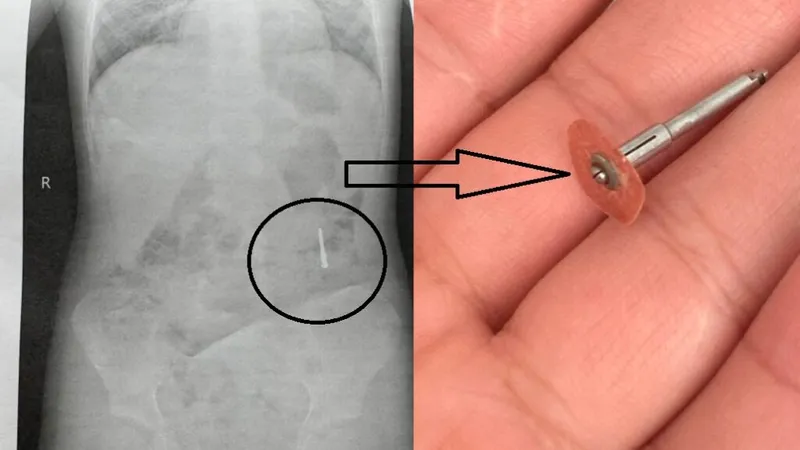

Incident stomatologic grav, copil la urgențe (sursa: ziaruldeiasi.ro)

Incident stomatologic grav, copil la urgențe. Un copil de 5 ani din Iași a ajuns la spital după ce a înghițit o freză metalică în timpul unei consultații stomatologice.

Incidentul a avut loc în cabinetul unui dentist, care le-ar fi spus părinților că micuțul a înghițit doar o hârtie abrazivă, ce urma să fie eliminată fără probleme.

Îngrijorați, părinții l-au dus la Spitalul „Sf. Maria”, unde radiografia a arătat prezența unui obiect metalic de peste 2 centimetri.

Familia susține că este vorba despre o freză dentară scăpată accidental în timpul tratamentului.